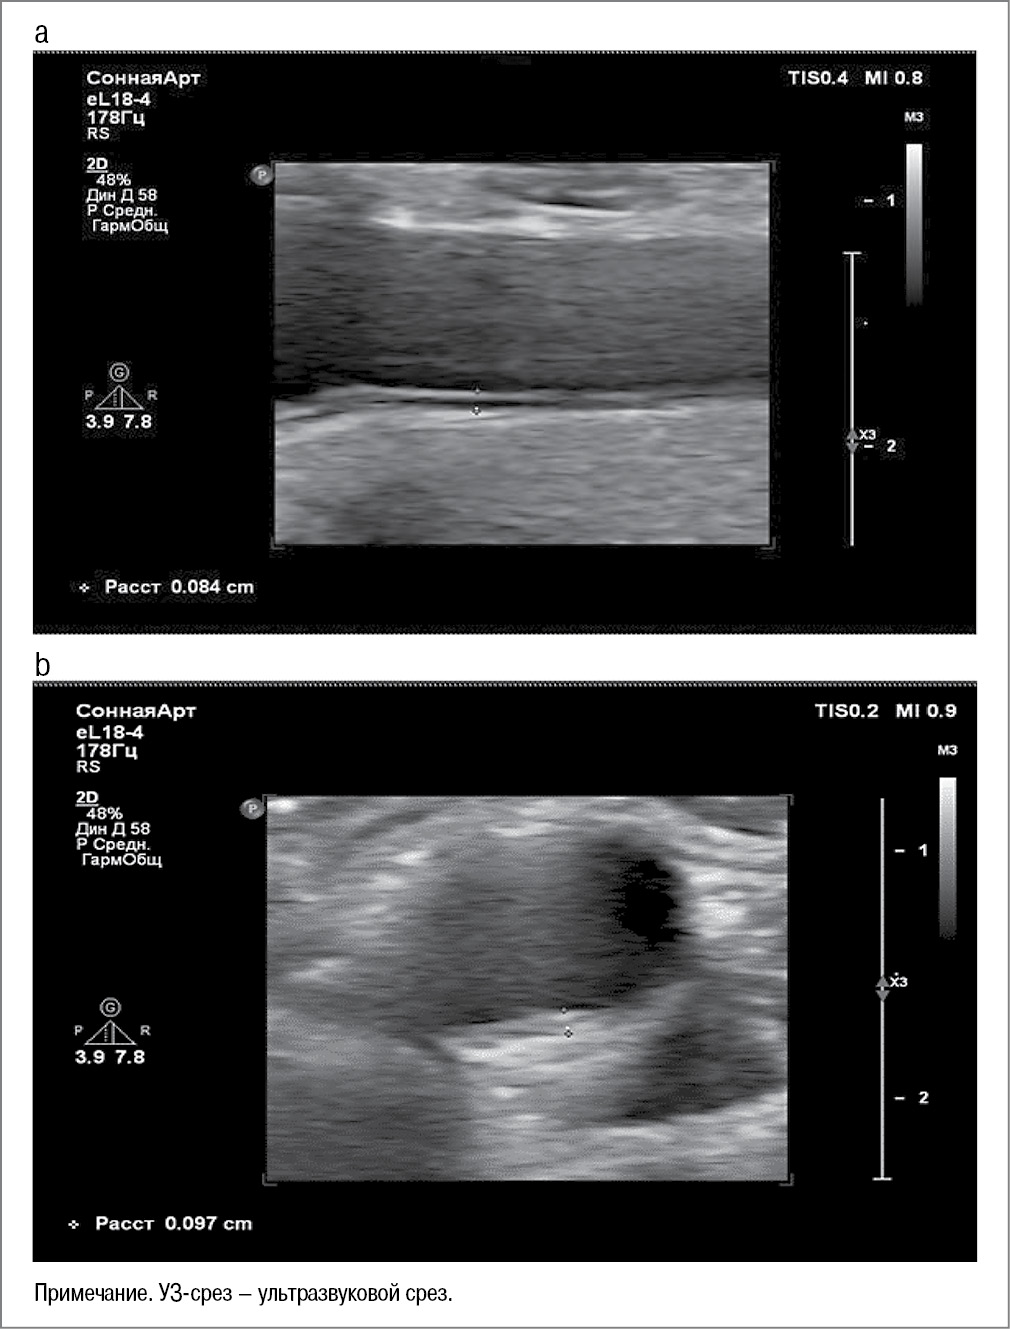

Одним из основных структурных показателей артериальной стенки является определение толщины комплекса интима–медиа (КИМ) в миллиметрах. Измерения показателей толщины КИМ производили согласно международным рекомендациям по ультрасонографии на расстоянии 1,0–1,5 см от бифуркации общей сонной артерии (ОСА).

Учитывали толщину КИМ ОСА в поперечном и продольном срезах, при этом неблагоприятным маркером считали ее величину более 1 мм. Акцент делали на появлении таких изменений, как извитость, неравномерное утолщение артерий, сужение просвета сосудов и появление атеросклеротических изменений (бляшек); рис. 1.

Рис. 1. Ультразвуковая оценка толщины КИМ ОСА: а – продольный УЗ-срез; b – поперечный УЗ-срез.

Fig. 1. Ultrasound assessment of the thickness of the intima-media complex of the common carotid artery (IMT-CCA): a – longitudinal view; b – transverse view.